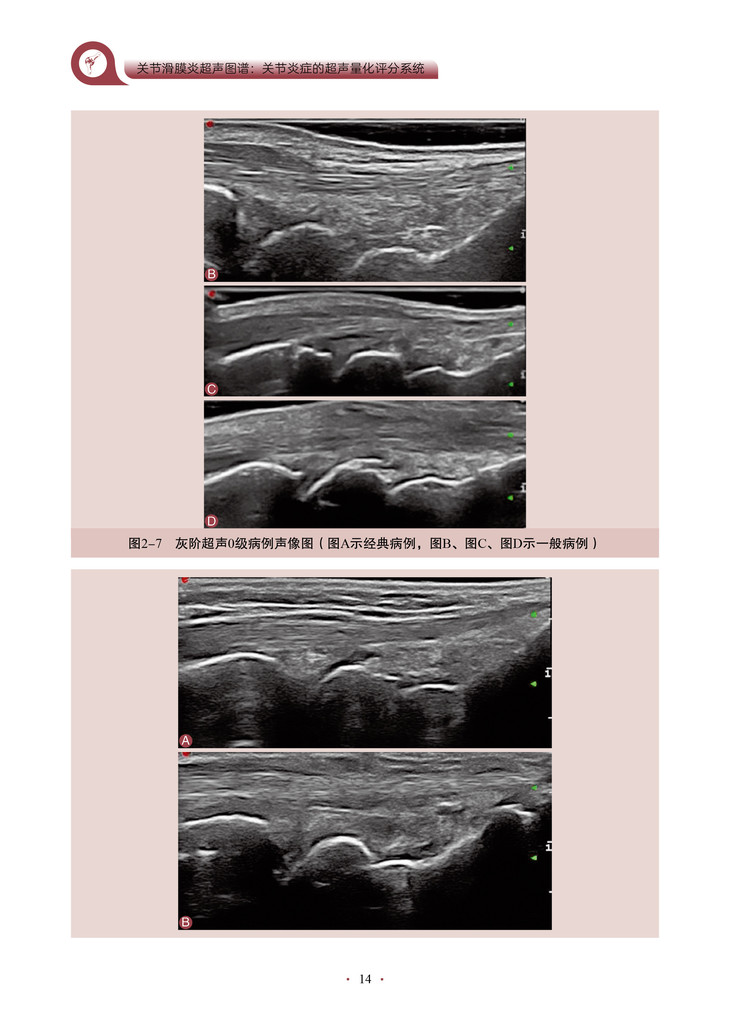

本书的核心内容是将超声技术应用于关节炎程度的评估,特别是对关节滑膜炎症的评分和客观量化。通过详细地介绍超声评分系统的构建和应用,作者为我们展示了一种全新的、基于客观指标的关节炎评估方法。该书深入探讨了关节滑膜超声图像的解读和分析,教导读者如何识别和评估关节炎引起的滑膜病变。通过使用可靠的超声评分系统,医师和研究人员能够更准确地量化关节炎患者的炎症程度和疾病进展,从而更好地指导治疗和监测疗效。